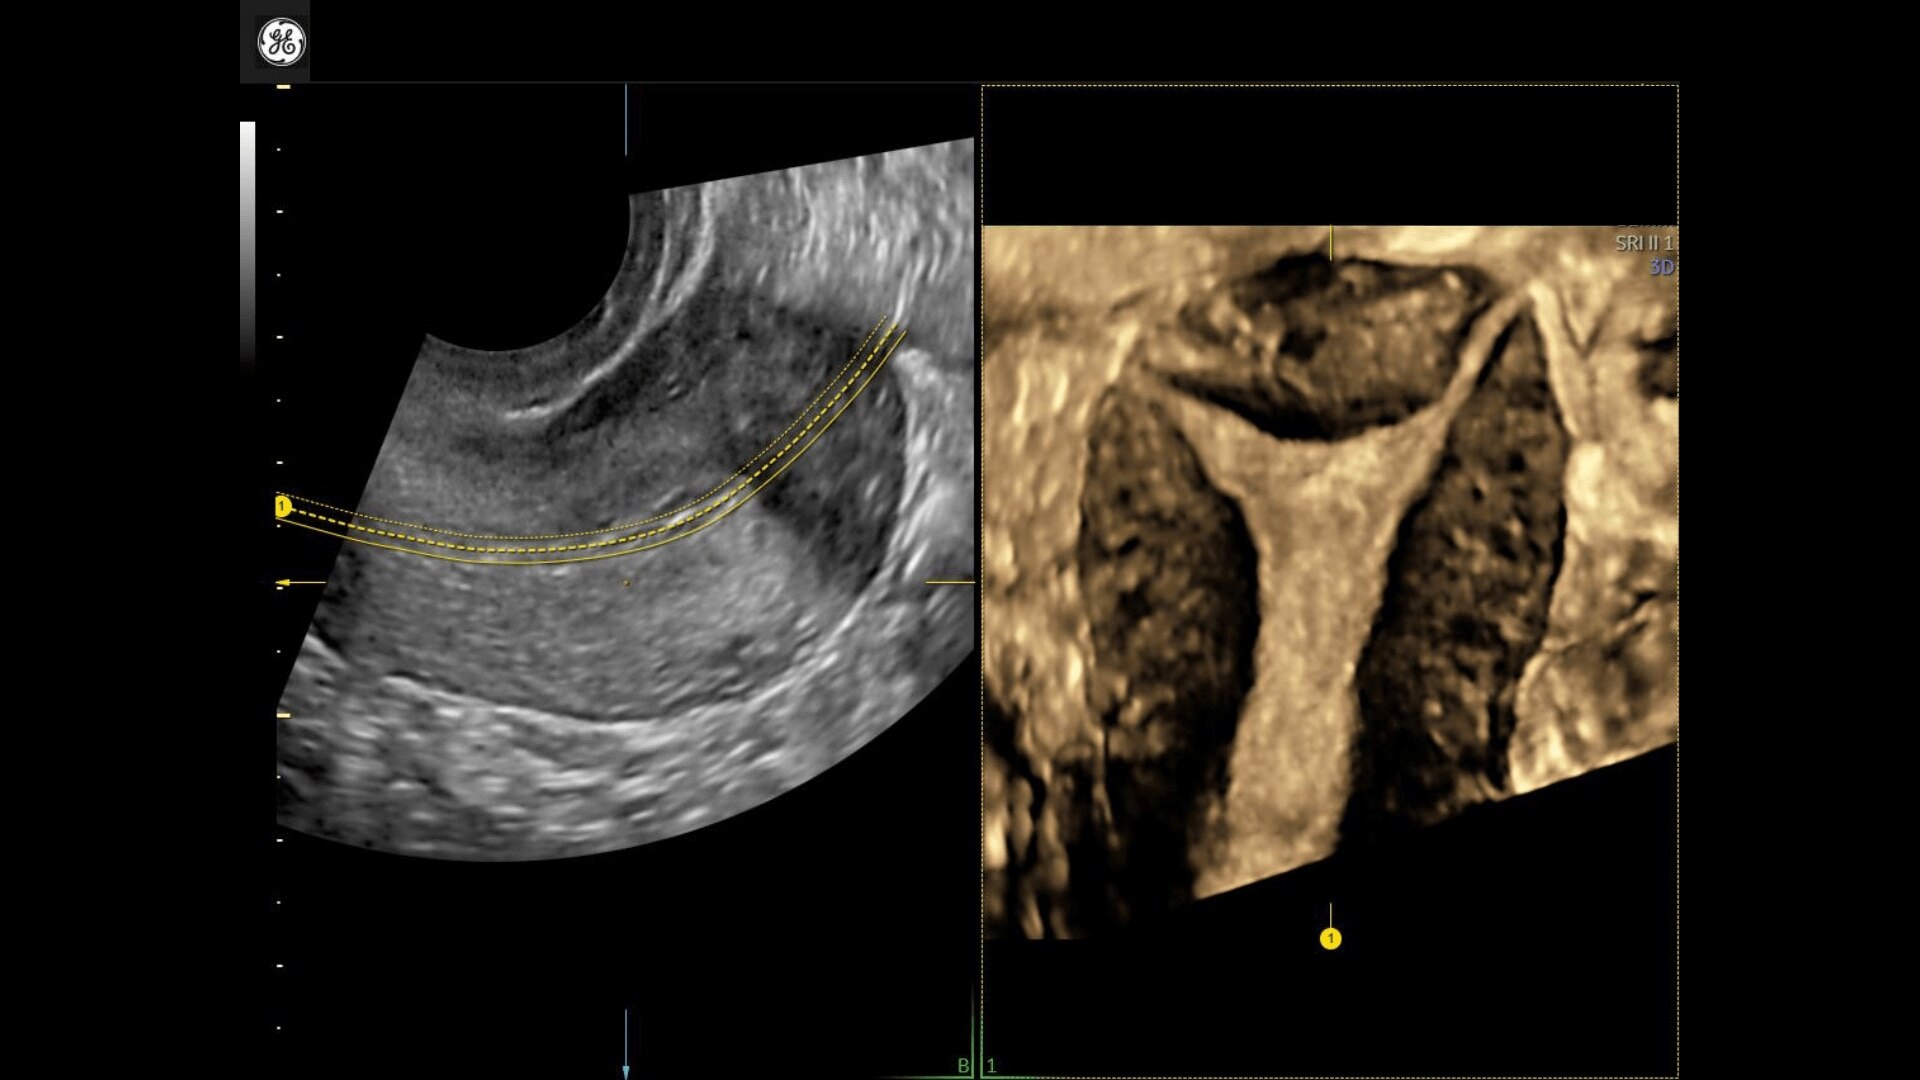

Uterine Trace

Easy display coronal view of uterus.

• Uterine Trace acquires the volume & then displays the coronal view of the uterus to simplify identification & reporting of uterine malformations.

• Uterine Trace acquires the volume and then displays the coronal view of the uterus linking to ASRM, ESHRE and ESGE Uterine Classification guidelines to simplify identification and reporting of uterine malformations